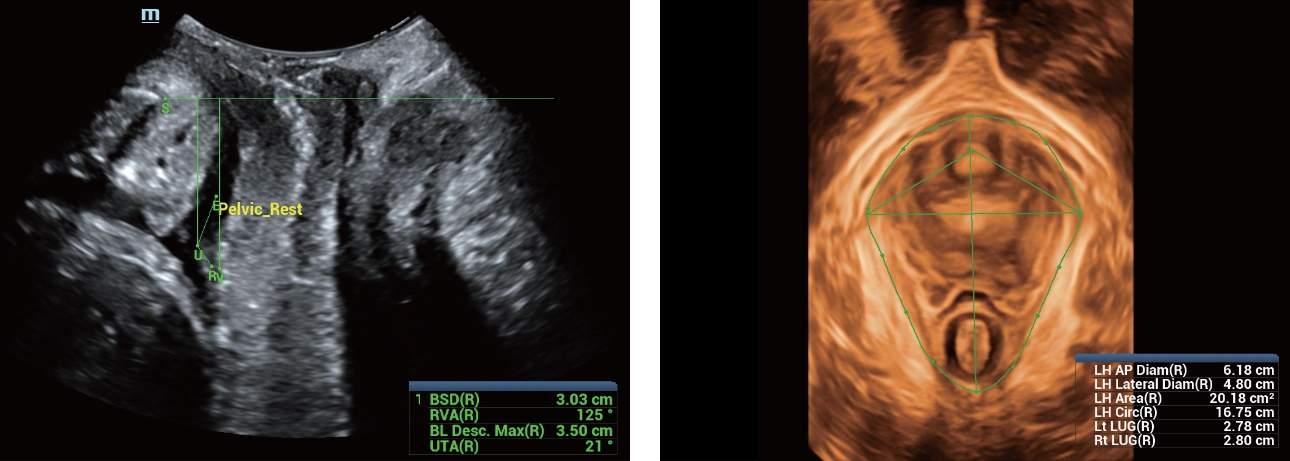

As well as the premium level image quality, Resona 7 also enhances clinical research capabilities with the revolutionary V Flow for vascular hemodynamic evaluation, and the most intelligent plane acquisition from 3D datasets for fetal CNS diagnosis. Combining the most intuitive gesture-based multi-touch operation and all the essential clinical features, Resona 7 is truly leading new waves in ultrasound innovation.